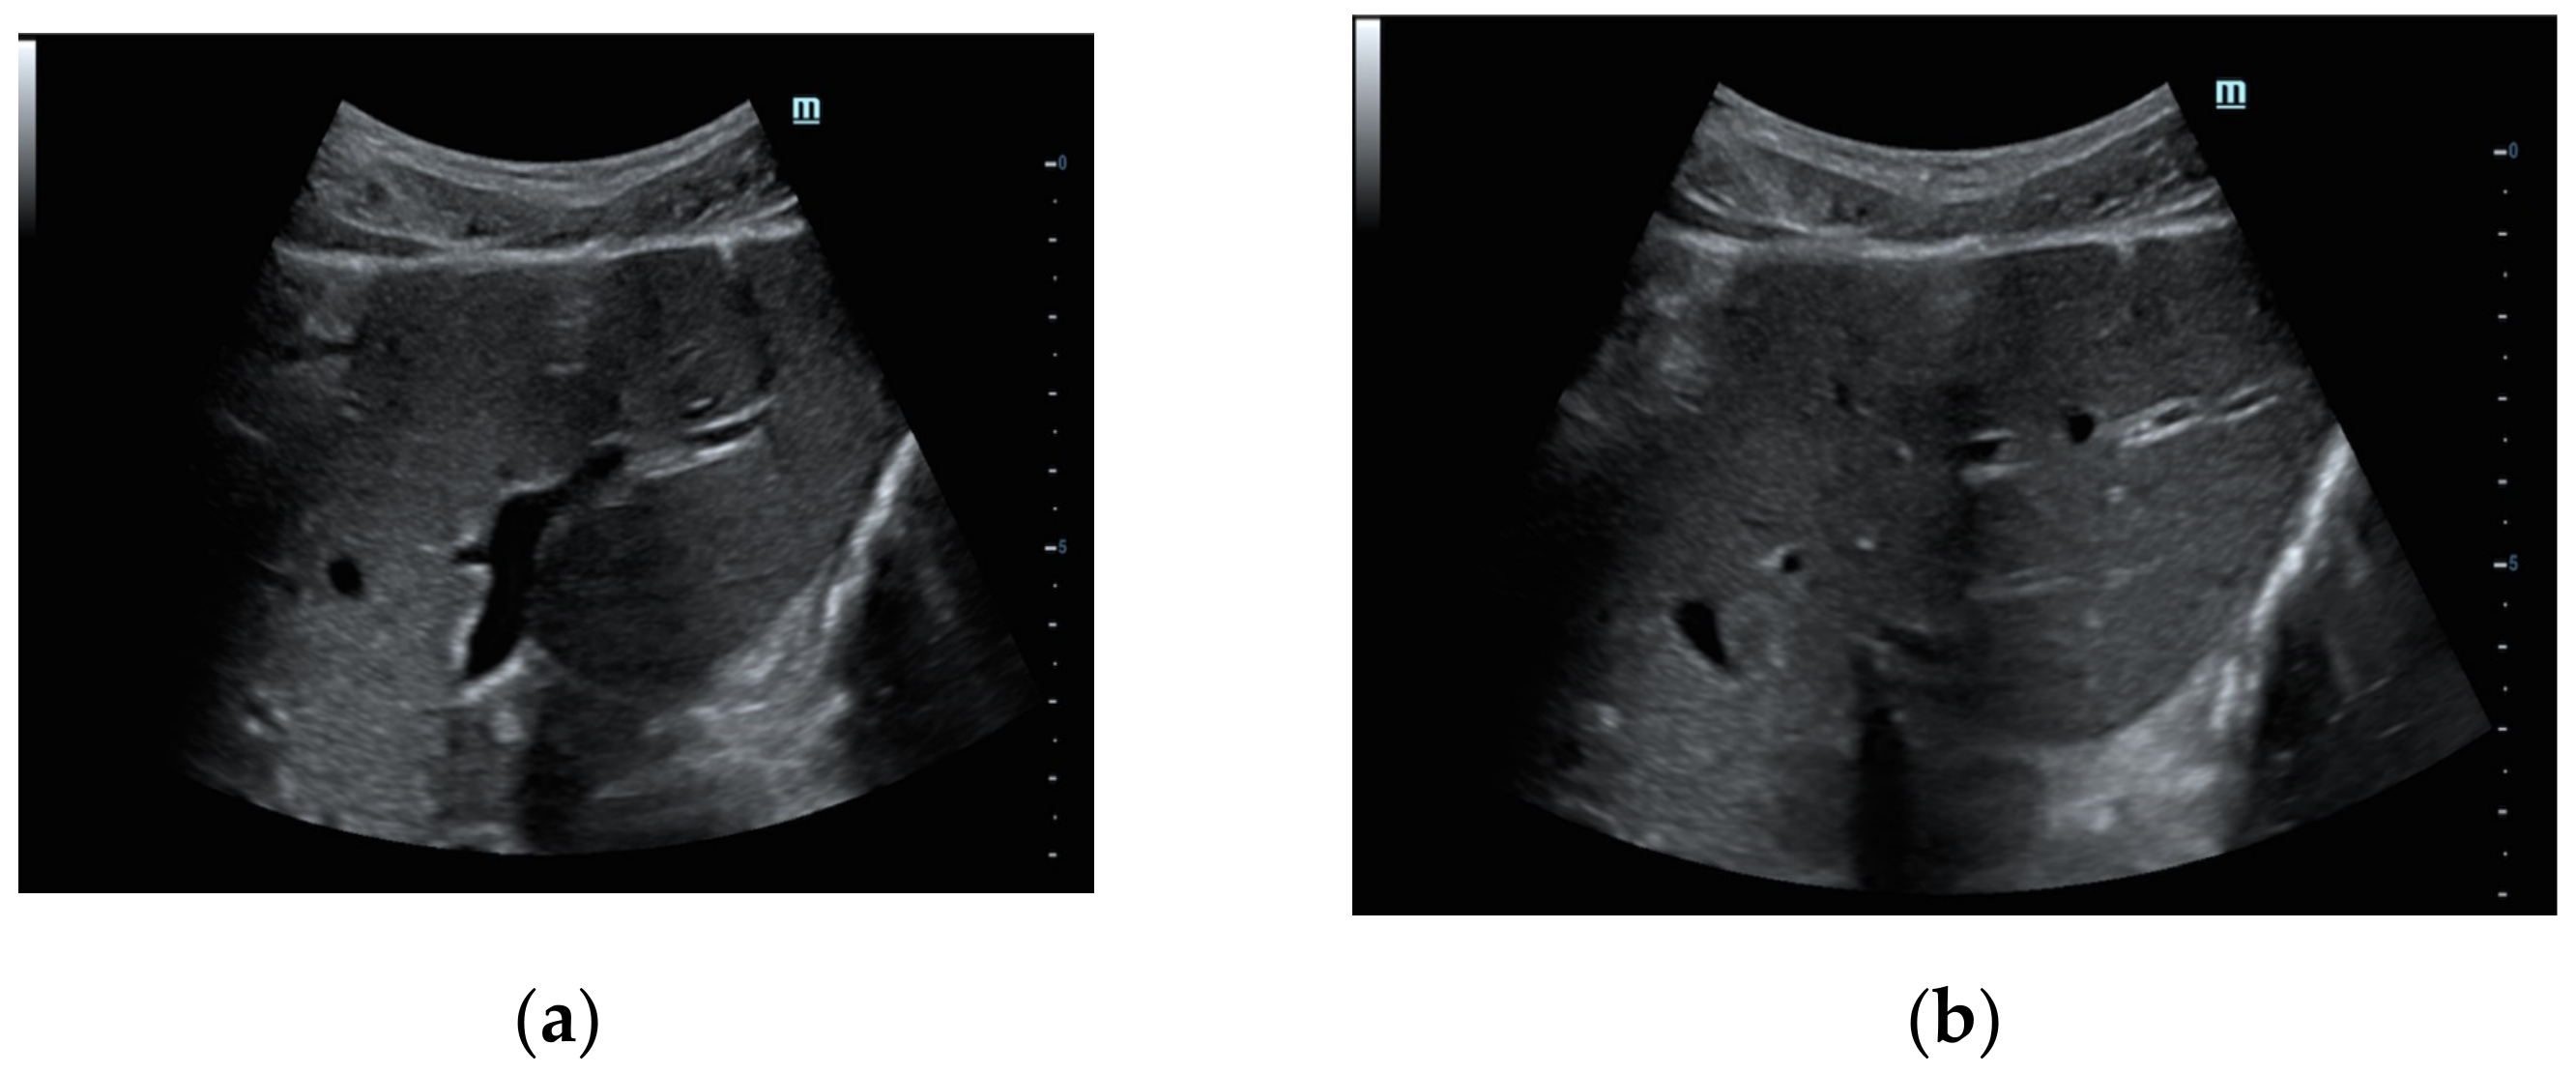

In our patients, larger air bubbles appeared as bright, highly echogenic lines with distal reverberation and shadowing artifacts, as ring-down or comet-tail artifacts on B-mode

(

Figure 2a); free air can also be detected beneath the anterior abdominal wall, where it generally accumulates in the supine patient (

Figure 2b).